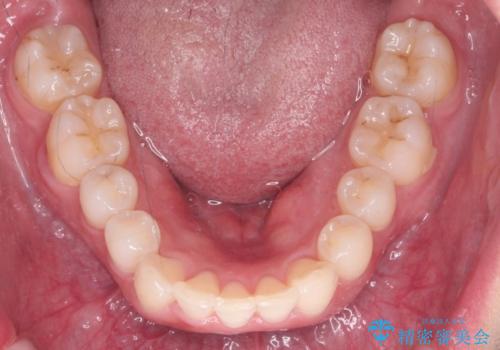

前歯をさげたい 歯を抜かずに マウスピース矯正で治したい

- 上の前歯が出ているとのことで来院。

歯を抜かずに、上の奥歯を後ろにさげつつ上の前歯を小さく少し削る処置を行い前歯の角度を修正しました。

右上下の奥歯もすれ違い咬合も、治療で改善しています。

下の前歯が生まれつき3本でしたので上下の正中は合わない仕上がりとなります。